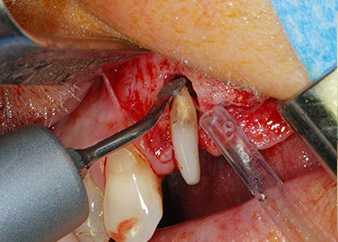

One month later, on the day of surgery, pain and inflammation at tooth 24 were minimal, but mobility of Miller class 2 was still present. After opening the flaps and cleaning the periapical and peri radicular infected tissue, the extent of the bone defect became obvious (Figs. 2 and 3).

At the buccal root, all vestibular and distal bone was missing. Attachment was essentially restricted to the palatal root, underlining the preliminary poor prognosis. Tooth 27 also showed a reduced horizontal attachment and a minimal apical rarefaction (cf. Fig. 1) without clinical symptoms.

Fig. 2 and 3: After raising flaps, one month after endodontic revision and initiation of full-mouth periodontal therapy, the buccal root of tooth 24 showed a total loss of bone and attachment.